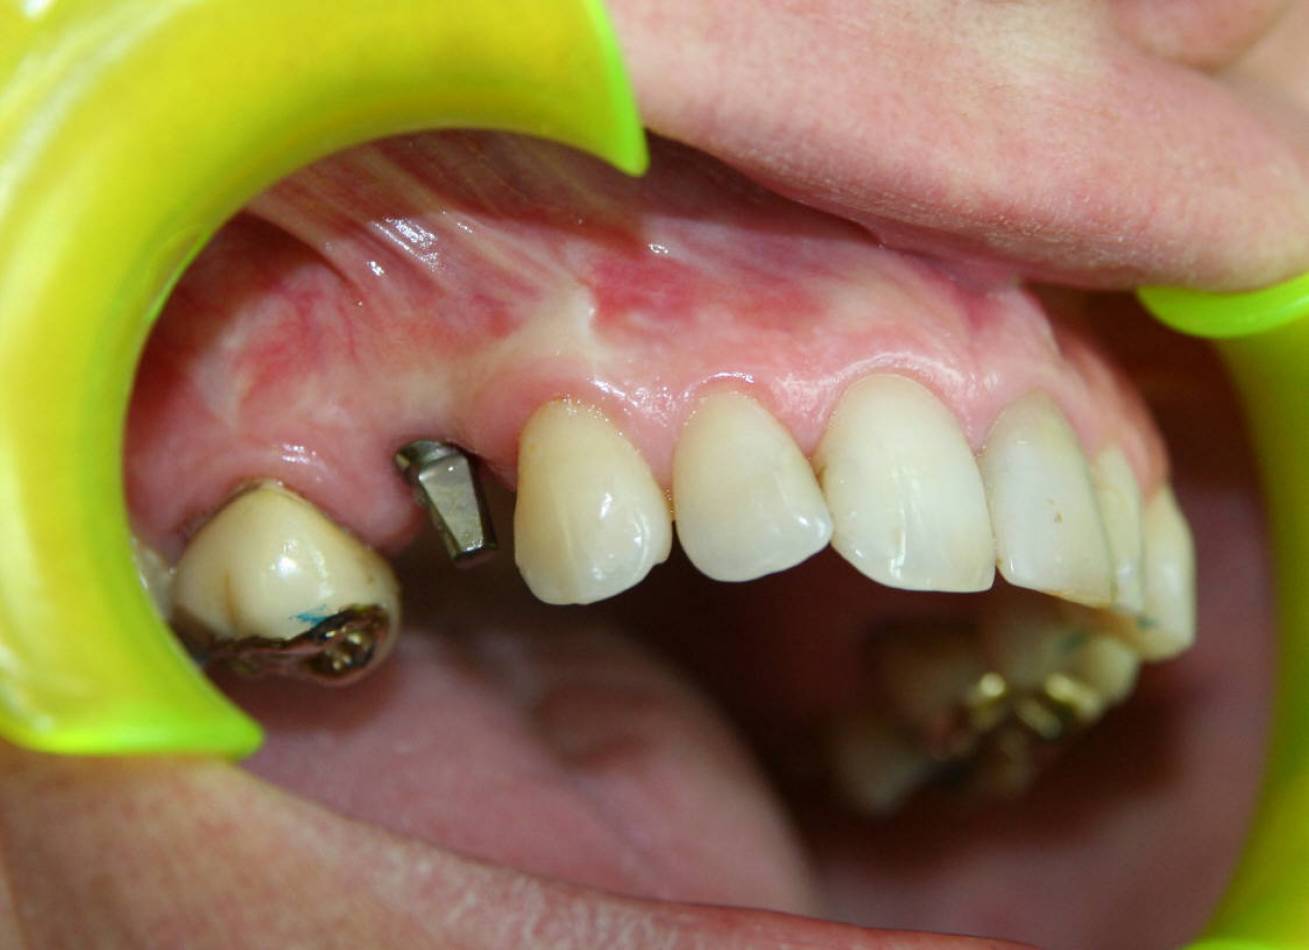

Implantologia e Chirurgia

Si effettua implantologia con impianti STRAUMANN e tecnologia IDI EVOLUTION.